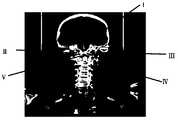

根据本申请的一些实施例,图13-G至13-M所示的是确定头颈部目标血管的感兴趣区域的另一组示例性实验结果图。所述头颈部目标血管包括颈内动脉穿颅段血管、椎动脉穿颅段血管、椎动脉穿椎段血管和基底动脉。其中,图13-G所示为颈内动脉穿颅段血管的感兴趣区域的定位效果图,图中G1、G2区域为所述颈内动脉穿颅段血管的感兴趣区域的掩膜。图13-H为示为椎动脉穿颅段血管的感兴趣区域的定位效果图,图中H1、H2区域为所述椎动脉穿颅段血管的感兴趣区域的掩膜。图13-I和图13-J所示为椎动脉穿椎段血管的感兴趣区域的定位效果图,图中方框区域为所述椎动脉穿椎段血管的感兴趣区域的掩膜。图13-K为所示为基底动脉的感兴趣区域的定位效果图,图中方框区域为所述基底动脉的的感兴趣区域的掩膜。图13-L所示为确定了所述目标血管感兴趣区域的图像(如图中I、II、III、IV、V所示)。图13-M为所述目标血管的感兴趣区域的三维立体显示图(左/右)(如图中I、II、III、IV、V所示)。In accordance with some embodiments of the present application, illustrated in Figures 13-G through 13-M are another set of exemplary experimental results plots that determine regions of interest of the head and neck target blood vessels. The head and neck target blood vessels include the internal carotid artery cranial segment blood vessel, the vertebral artery transcranial segment blood vessel, the vertebral artery penetrating segment blood vessel, and the basilar artery. Among them, Fig. 13-G shows the positioning effect of the region of interest of the internal carotid artery through the cranial segment, in which the G1 and G2 regions are the masks of the region of interest of the internal carotid artery cranial segment. . Fig. 13-H is a view showing the localization effect of the region of interest of the vertebral artery cranial segment blood vessel, in which the H1 and H2 regions are masks of the region of interest of the vertebral artery cranial segment blood vessel. Fig. 13-I and Fig. 13-J show the positioning effect of the region of interest of the vertebral artery through the segmental blood vessel, in which the boxed region is the mask of the region of interest of the vertebral artery through the segmental vessel. Figure 13-K is a view showing the positioning effect of the region of interest of the basilar artery, in which the boxed region is the mask of the region of interest of the basilar artery. Figure 13-L shows an image of the region of interest of the target vessel (shown as I, II, III, IV, V in the figure). Figure 13-M is a three-dimensional stereoscopic view (left/right) of the region of interest of the target vessel (shown as I, II, III, IV, V in the figure).